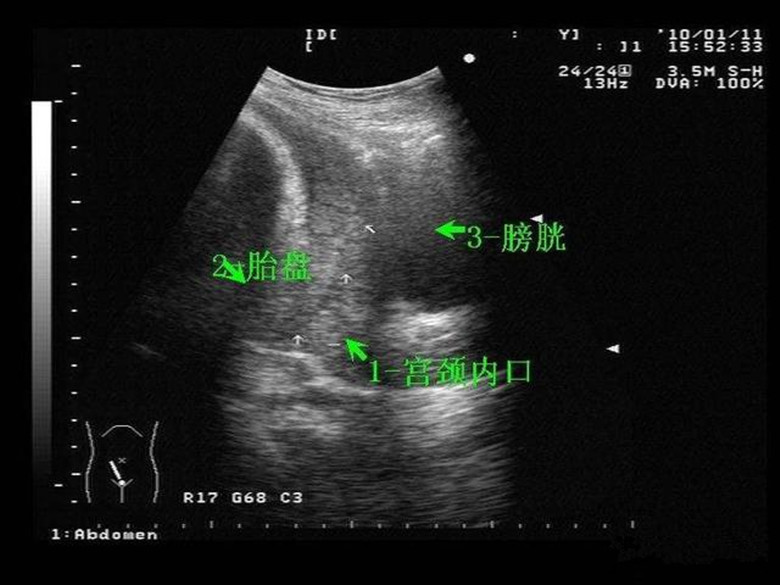

什么是前置胎盘呢?受精卵着床之后,先是出现孕囊,然后孕囊发育成为胎盘。所以,胎盘是很早就固定了。正常的胎盘,应该远离宫颈内口。胎盘种植在子宫前壁、后壁、侧壁或者宫底,这都是正常的情况。异常的情况是:如果胎盘的位置靠近宫颈内口小于2cm,或者胎盘有一部分或者全部覆盖到宫颈内口了,这就是比如麻烦的前置胎盘了。

前置胎盘的原因是什么?1,主要原因:是多次妊娠,或者多次人工流产,从而导致子宫内膜太薄。子宫内膜太薄,血供就不足。怎么办呢?为了获得更的营养,胎盘就会扩大附着面积,或者主动向血供充足的地方靠近。而孕早期的子宫非常小,这样胎盘长着长着,就接近宫颈内口了。2,孕妇如果有宫腔炎症、瘢痕子宫或者有子宫肌瘤,这些地方都不利于胎盘发育,这样受精卵着床也会向子宫下段靠近,就成了前置胎盘了。

孕妈有前置胎盘,怎么办呢?1,判断是否前置胎盘,以怀孕28周为界线。28周之前,前置胎盘不要紧,28周之后随着子宫下段延展,胎盘一般都会长上去。2,28周之后,如果经检查确诊为前置胎盘,那就要绝对卧床!禁止同房!并且还要注意预防胎盘早剥和出血。3,选择一家三甲医院提前备血,并在医生指导下补铁:补铁是为了避免失血过多,而铁元素能增加血液的含氧量,预防胎儿缺氧或窒息。4,请在医生指导下补锌:锌元素能增加胎盘的弹性,降低胎盘早剥风险,预防胎儿早产。5,备孕期间就要提前治疗宫腔炎症,如果头胎是剖宫产应该间隔2年以上。边缘性前置胎盘可以顺产,不过风险较大,建议孕妈还是提前做好剖宫产的准备。